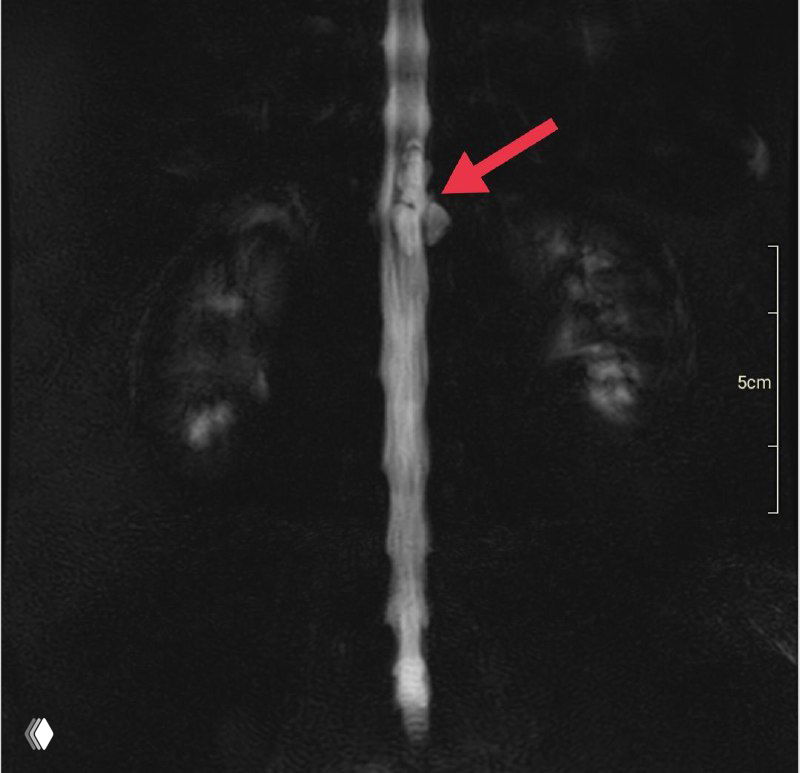

Установка игл Джамшиди перед вертебропластикой

Фото установки игл Джамшиди в тело позвонка перед пункционной вертебропластикой: проколы кожи, рентген‑контроль и последующее введение костного цемента.